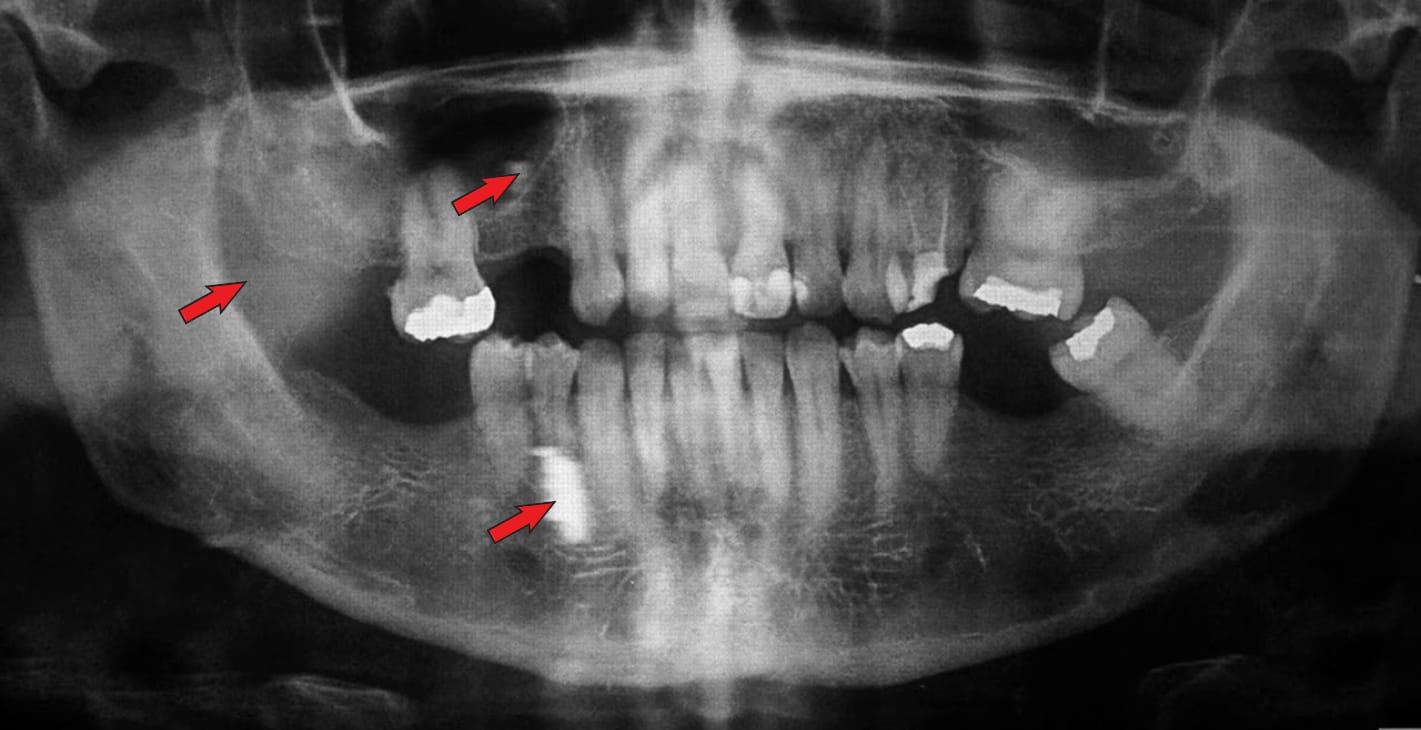

Immagine 1: immagine fantasma

Immagine 2: è visibile un corpo estraneo che corrisponde al grembiule di piombo.